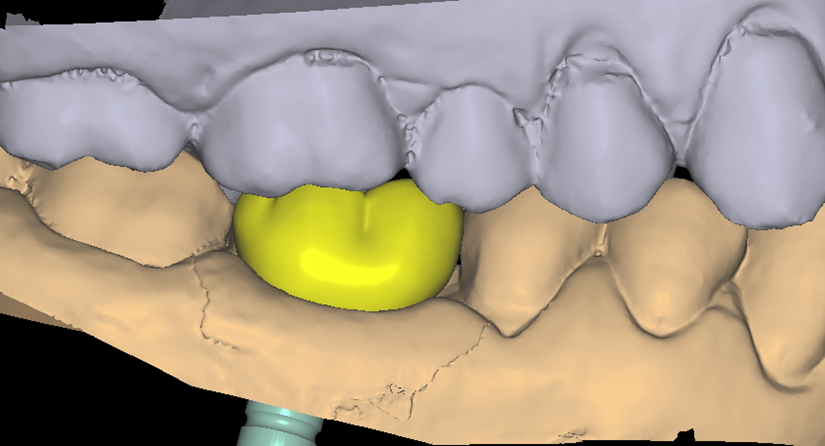

O paciente apresentou fratura vertical mésio-distal no elemento 46. Foi planejada a exodontia minimamente traumática e instalação imediata do implante Maestro Superiore (Implacil Osstem) utilizando uma guia prototipada. Após a exodontia, o implante foi instalado seguindo o protocolo de cirurgia guiada. O GAP vestibular foi preenchido com o Extra Graft. Um cicatrizador personalizado impresso com haletas facilitadoras foi capturado com resina flow e instalado. Após 30 dias, foi realizado escaneamento indireto para obtenção do perfil de emergência, utilizando protocolo digital com sobreposição do cicatrizador escaneado para confecção da coroa definitiva em zircônia policristalina estabilizada por ítria.

Etapas de personalização do cicatrizador e escaneamento

O uso de cicatrizadores personalizados, especialmente confeccionados por impressão 3D, tem ganhado destaque por permitir a conformação tecidual progressiva, facilitando a reprodução do perfil de emergência no fluxo digital6,7. A captura do cicatrizador com haletas de retenção com resina flow e seu posterior escaneamento são etapas críticas para assegurar a fidelidade da transferência do perfil de emergência e garantir um planejamento restaurador mais previsível8.

Neste caso, a sobreposição digital entre o cicatrizador escaneado e o desenho da coroa possibilitou comparar perfis de emergência com excelente adaptação clínica, contribuindo para um resultado estético e funcional adequado.